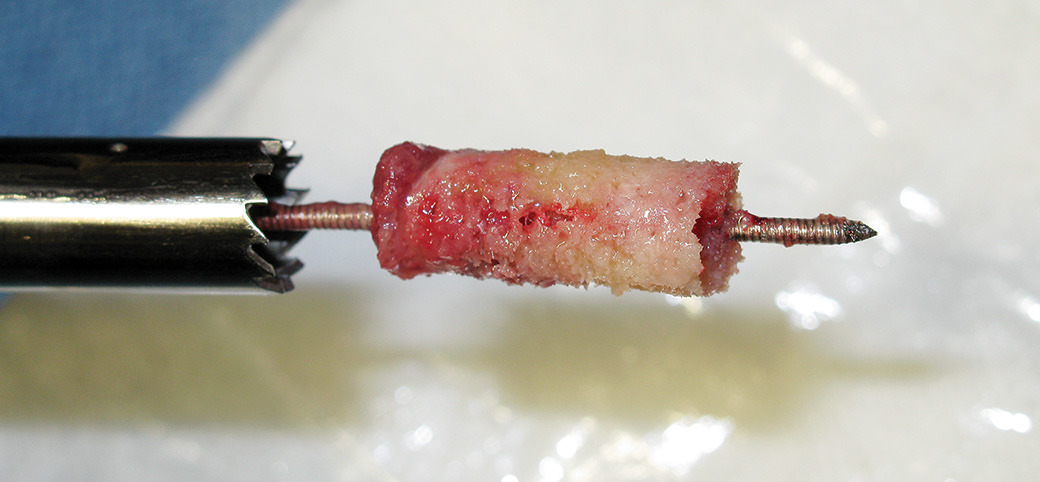

Cannulated T-handle and trephines allow use of a standard 1.6 mm (.062″) threaded K-wire to help facilitate grasping and removal of a core bone sample for biopsy or core decompression

- • Variety of core diameters yields bone samples of sufficient size for pathology

- • Can also be used for bone graft harvesting